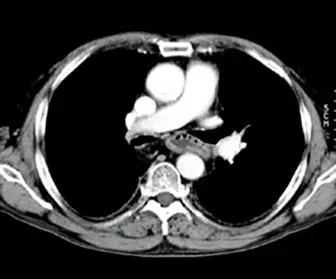

觀察題目提供的胸部 CT 橫斷面影像,具備以下特徵:

- 肺部實質(Lung parenchyma):呈現完全黑色,無法看見任何肺紋、血管或支氣管等細節,這代表肺部組織的 HU 值(約 -500 至 -900 HU)遠低於該影像窗寬的下限。

- 縱膈腔結構與軟組織(Mediastinum and soft tissues):縱膈腔內的大血管(升主動脈、降主動脈、肺動脈幹)因含有對比劑而呈現高亮。血管與周邊的縱膈腔脂肪、肌肉層之間具備極佳的灰階層次與對比度。

- 骨骼系統(Bones):肋骨、胸骨與脊椎呈現高亮度的全白,無法看清內部的骨小梁與骨髓腔細節,代表骨骼的 HU 值已超出該窗寬的上限。

綜合以上特徵,這是一張用來觀察胸部軟組織與心血管結構的標準**縱膈腔窗(Mediastinal window)**影像。

- (C) WW: 500、WL: 40:此數值為典型的縱膈腔窗(Mediastinal window)。其顯示範圍為 -210 到 290 HU。肺臟(-500 HU 以下)低於下限呈全黑;骨骼與含對比劑的血管(> 300 HU)高於上限呈全白;而縱膈腔脂肪、肌肉等軟組織(-100 到 60 HU)恰好落在灰階範圍的中心區間,能展現絕佳的軟組織對比。與影像特徵完全吻合。

根據影像分析,我們清楚地看到具有良好灰階對比的縱膈腔軟組織、全白的骨骼以及全黑無細節的肺野。套用上述計算:只有選項 (C) 的設定範圍(-210 ~ 290 HU)能夠讓肺部組織低於下限(全黑),同時讓軟組織落在灰階漸層區間內完美顯示,因此 (C) 是最正確的答案。